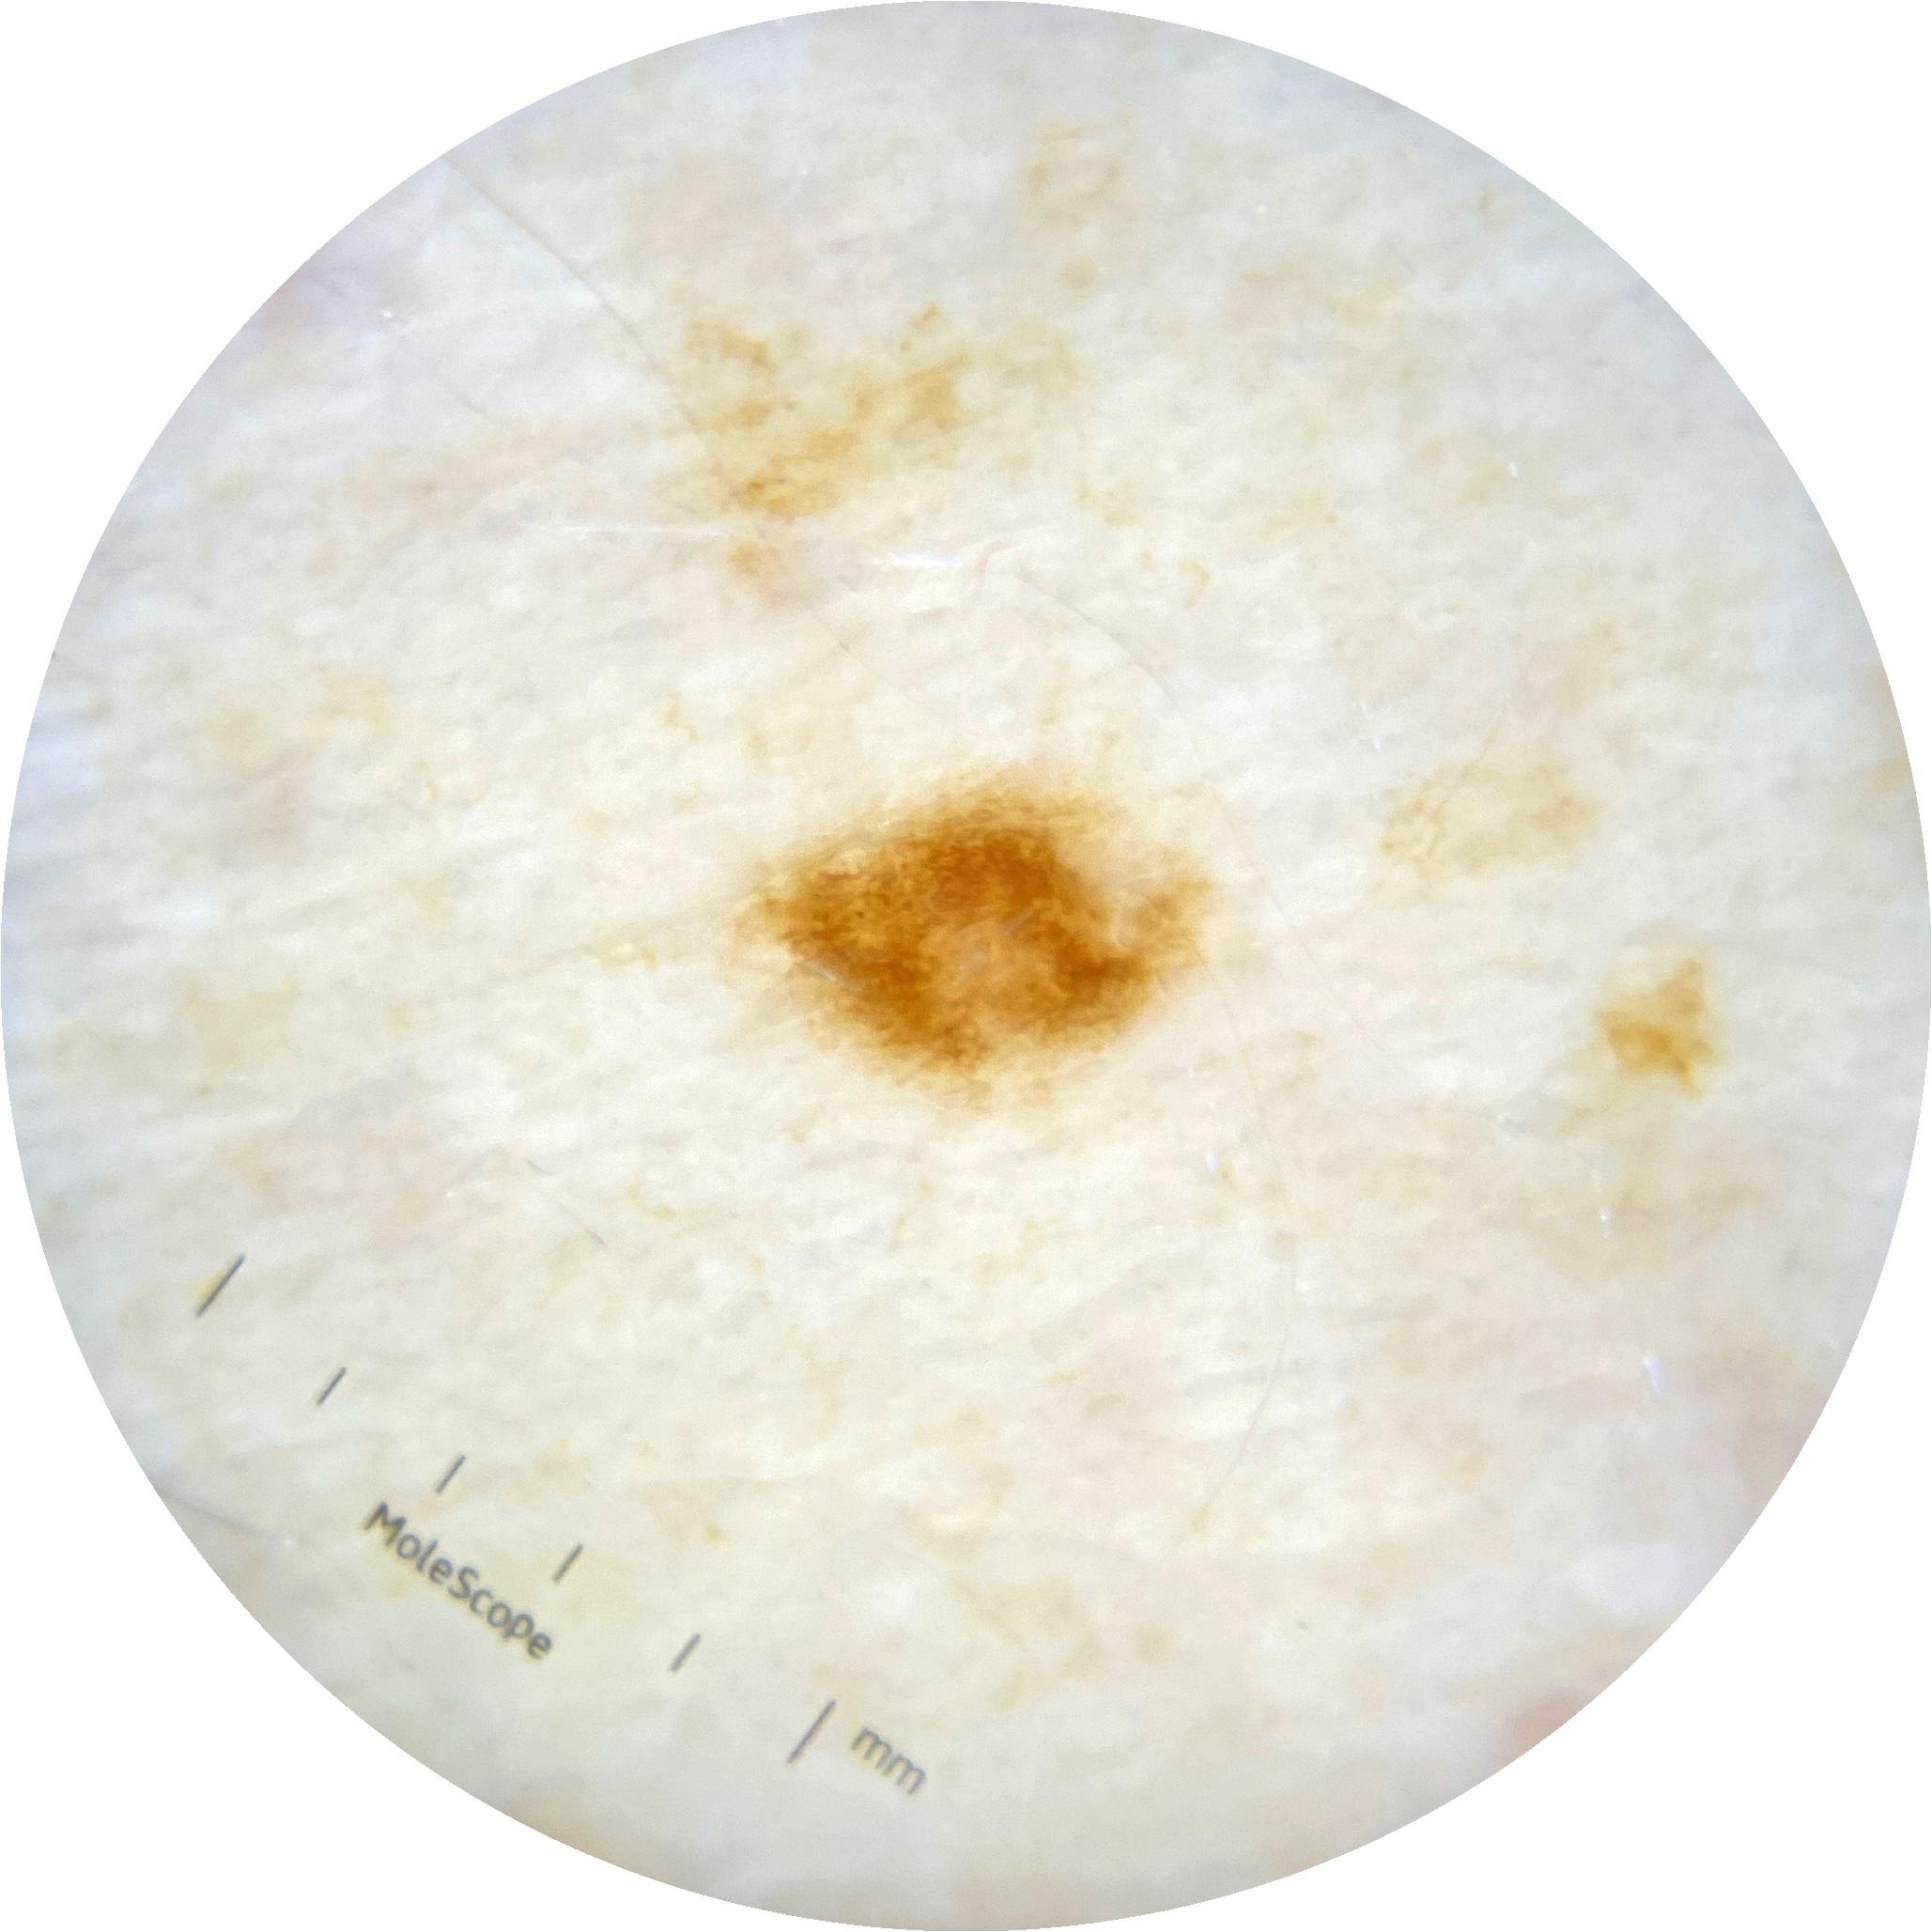

ISIC_2261268

acquisition_day 307

age_approx 50

anatom_site_1 Trunk

anatom_site_2 Posterior trunk

anatom_site_general posterior torso

diagnosis_1 Benign

diagnosis_confirm_type single image expert consensus

image_type dermoscopic